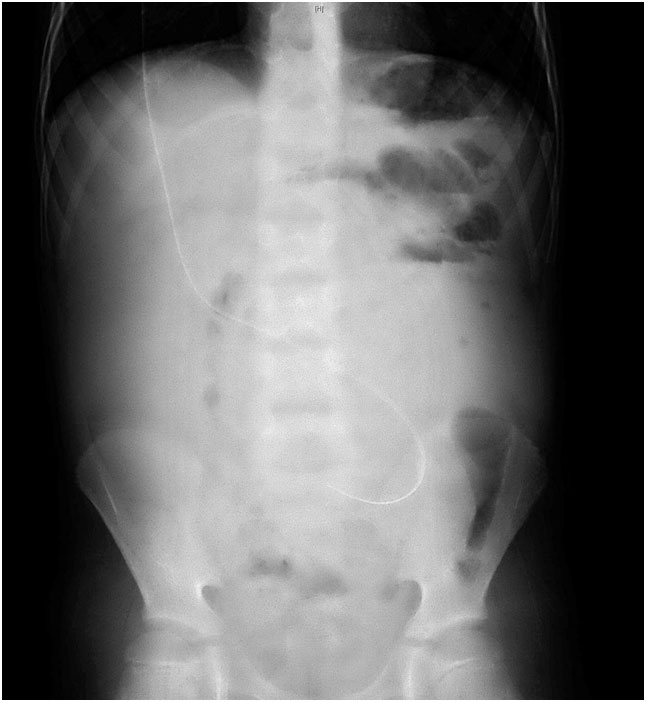

An 8-year-old male VP shunt case presented to us at Gaziosmanpasa University Hospital in 2013 with abdominal distension and vomiting. Because of congenital hydrocephalus, he had five shunt operations, first one in the newborn period, and two times third ventriculostomy procedures. The patient had a history of increasing abdominal distention during the last two months. We examined the patient and determined a giant cystic mass filled with fluid which was enclosing the distal shunt tip and pushing the intestines close to the lateral walls of the abdomen at plain abdominal graph [Table/Fig-1]. Laparoscopic fenestration was performed on the cyst with parental informed consent. The abdominal distension recurred during the first month after the operation and we applied laparotomy followed by cyst excision and intestinal adhesiolysis, while the distal shunt tip was placed in the pelvis. About three litres of fluid was removed from the pseudocyst enclosing the distal shunt tip.

Plain abdominal graphy is the primary imaging method for the early diagnosis of IP cases [11]. One can see the contours of the fluidfilled cyst and the intestinal loops pushed to the lateral walls of the abdomen by the cyst. Ultrasonography (US) is also an easy and quick method for diagnosis of IP [12]. US can reveal the fluid-filled cyst harboring the distal catheter tip. The rail road track sign on the cyst wall is typical [3]. Since the diagnosis can be achieved easily via US, computerised tomography (CT) should be employed only in cases where US fails to reveal the cyst clear enough to establish a diagnosis. Moreover, it should be borne in mind that these children frequently receive cranial tomography and are exposed to high doses of radiation throughout their lives. In the present case, the plain abdominal graphy clearly showed the contours of the cyst and the lateralized intestinal loops. Moreover, US displayed the fluidfilled giant cyst, as well.

Plain abdominal radiography. Cystic mass filled with fluid which was enclosing the distal shunt tip and pushing the intestines close to the lateral walls of the abdomen